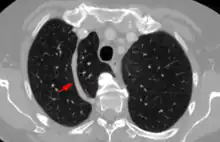

In human anatomy, an azygos lobe is a normal anatomical variation of the upper lobe of the right lung.[1] It is seen in 0.3% of the population.[2] Embryologically, it arises from an anomalous lateral course of the azygos vein,[3] in a pleural septum within the apical segment of the right upper lobe or in other words an azygos lobe is formed when the right posterior cardinal vein, one of the precursors of the azygos vein, fails to migrate over the apex of the lung and penetrates it instead, carrying along two pleural layers as the azygous fissure, that invaginates into the upper portion of the right upper lobe.[1]

An azygos lobe is usually an incidental finding on chest x-ray or CT scan. It is asymptomatic and not associated with any morbidity.[4][5] However, it can cause technical problems in thoracoscopic procedures.[6] The presence of the azygos lobe could alter the normal location of the superior vena cava or may be associated with other anomalies, including esophageal atresia or intrapulmonary right brachiocephalic veins.[7]